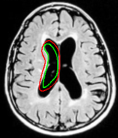

Refer to captionRefer to captionRefer to captionRefer to captionRefer to captionRefer to captionRefer to captionRefer to captionRefer to captionRefer to captionRefer to captionRefer to captionRefer to captionRefer to captionRefer to captionRefer to captionRefer to captionRefer to captionRefer to captionRefer to captionRefer to captionRefer to captionRefer to captionRefer to captionRefer to captionRefer to captionRefer to captionRefer to captionRefer to captionRefer to captionRefer to captionRefer to captionRefer to captionRefer to captionRefer to captionRefer to caption\begin{array}[]{cccccc}\includegraphics[width=72.26999pt]{Optimal-inti.pdf}&\includegraphics[width=72.26999pt]{Optimal-final.pdf}&\includegraphics[width=72.26999pt]{40.pdf}&\includegraphics[width=72.26999pt]{OAS1_0040_msp_niiSeg.pdf}&\includegraphics[width=72.26999pt]{140.pdf}&\includegraphics[width=72.26999pt]{OAS1_0140_msp_niiSeg.pdf}\\ \includegraphics[width=72.26999pt]{157.pdf}&\includegraphics[width=72.26999pt]{OAS1_0157_msp_niiSeg.pdf}&\includegraphics[width=72.26999pt]{168.pdf}&\includegraphics[width=72.26999pt]{OAS1_0168_msp_niiSeg.pdf}&\includegraphics[width=72.26999pt]{221.pdf}&\includegraphics[width=72.26999pt]{OAS1_0221_msp_niiSeg.pdf}\\ \includegraphics[width=72.26999pt]{237.pdf}&\includegraphics[width=72.26999pt]{OAS1_0237_msp_niiSeg.pdf}&\includegraphics[width=72.26999pt]{293.pdf}&\includegraphics[width=72.26999pt]{OAS1_0293_msp_niiSeg.pdf}&\includegraphics[width=72.26999pt]{395.pdf}&\includegraphics[width=72.26999pt]{OAS1_0395_msp_niiSeg.pdf}\\ \end{array}

Figure 12: Segmentation of corpus callosum images in sagittal plane T1-weighted brain magnetic resonance images taken from [37]. For all images, the same template was used and initialized in a manner similar to the way shown in the top left corner image. The converged results using the proposed shape template approach and the result obtained on subsequent refinement using snake energies[22] are displayed alongside.

In Figure 12, we show the results obtained for segmentation of corpus callosum in T1-weighted MR images. Many techniques on segmentation of corpus callosum are affected by the adjoining fornix structure due to the similarity in intensities. However, it can be observed from the results that the proposed snake is less affected by the fornix. We further refine results obtained using the proposed technique with gradient energies[22]. We display the results obtained on refinement alongside the output from the proposed shape-based approach.